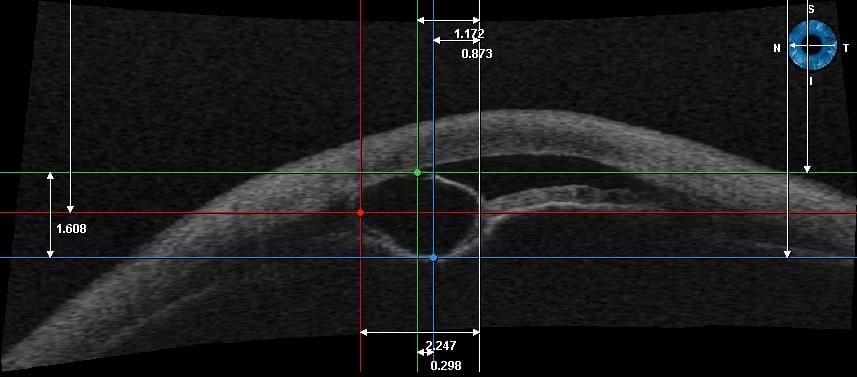

• modernste Messgeräte und Operationsmöglichkeiten

Rechtzeitige Premium-Diagnostik erlaubt uns rechtzeitige Interventionen

Viele Erkrankungen verlaufen unbemerkt über lange Zeit.

Daher muss mit technischen Mitteln eine umfassende Augenvermessung erfolgen, damit man frühzeitig reagieren kann.